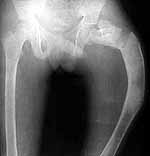

I am seeking help in managing a young patient 14 years old male with pathological subtrochanteric fracture neck femur. the problem is the severe varus deformity of the proximal femur the so called shepherd's crook deformity and also healing fracture shaft femur in midshaft region which he had sustained 6 months ago and was treated conservatively elsewhere. patient wants his deformity correction along with his fracture treatment if possible.

photo

The patient is delighted and working hard on knee flexion and has acheived up to 90 degrees now. Histopathology has come back as fibrous dysplasia. I am attaching the pre op and post op xrays.

preop